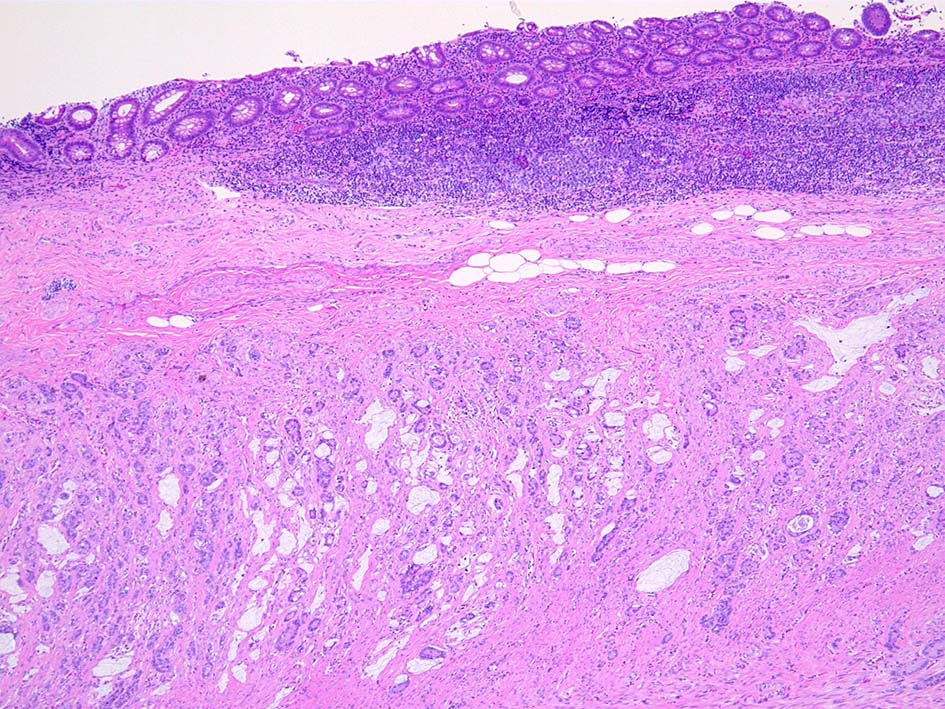

組織所見